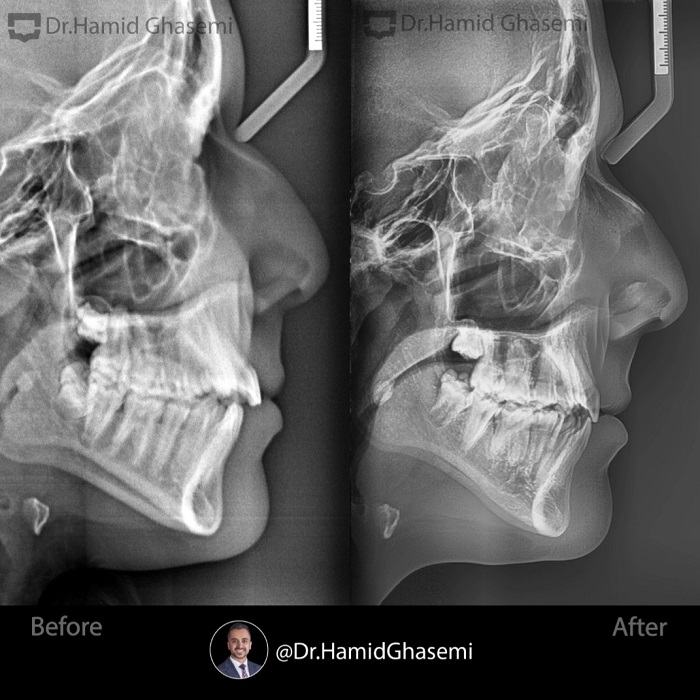

درمان ارتودنسی بدون جراحی فک در کیس اپن بایت همراه با تنگی فک بالا در مدت ۲۰ ماه انجام شد.

None surgical orthodontic treatment of openbite case with upper arch constriction done within 20 months.